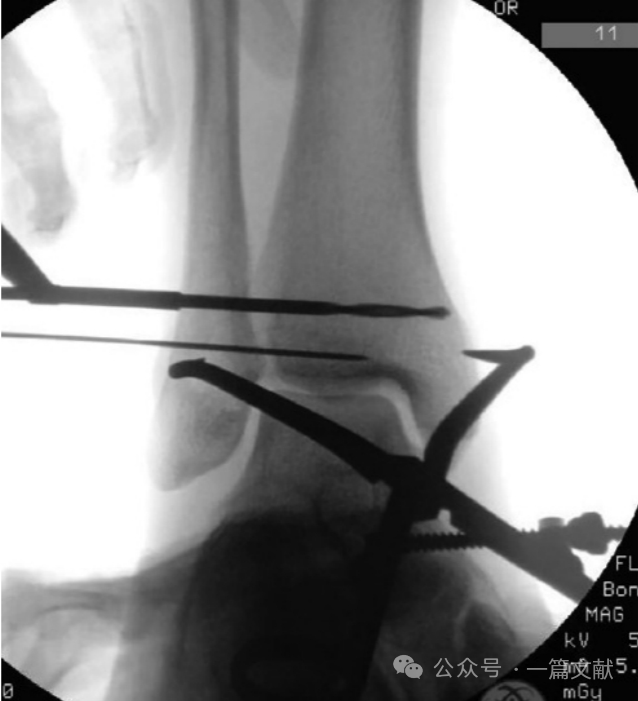

这张对比图像的重点是观察腓骨与胫骨的前后方向相对位置,来判断腓骨是否有前后移位。以及腓骨的投影大小,来判断腓骨是否有旋转。当克氏针穿透腓骨并进入胫骨切迹时,复位钳轻轻夹持复位,此时要避免过度复位。

图片